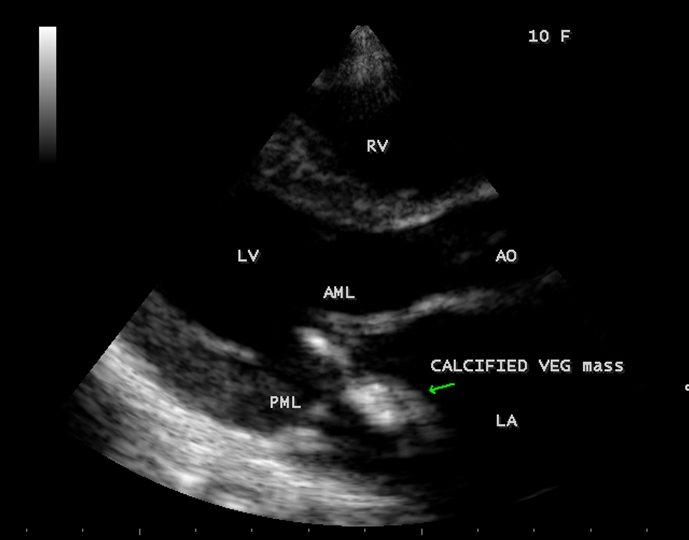

The most common and direct evidence of infective endocarditis is the vegetation and it begins as a microscopic focus of infection and gradually grows into a conspicuous mass. It is typically an irregularly shaped, highly mobile, echogenic mass attached to the free edge of a valve leaflet ( most commonly at the coaptation line) and tends to develop on the ‘upstream’ side of the valve leaflets ( ie, the ventricular side of aortic valve and the atrial side of mitral and tricuspid valves. They may be seesile or pedunculated, but usually has an oscillating or fluttering motion, a typical feature of most vegetations. Vegetation move with the leaflet in a more chaotic (‘oscillating’) manner and it may prolapse through the valve into the LV (left ventricle) as it opens as shown in Figures 3, 4 and 16 and into LA (left atrium) as it closing (Figure 5 and 6) . The mass of vegetation is typically homogeneous with echogenicity similar to that of the myocardium. The infectious process often alter the valvular structure and function. Extensive involvement of the leaflet may result in chordal rupture, leading to severe regurgitation as shown in Figure 21 . Direct and typical signs of RMCT (ruptured mitral chordate tendineae) were chain-flail or whiplash-like changes and had an incidence of 86.7%, causing severe regurgitation and mitral chordal rupture is the leading cause of flail mitral leaflet[30]. A large vegetation may obstruct the valve orifice as shown in Figure 1 and 2 , sometimes termed as “obstructive-type bacterial endocarditis” and producing a functional valve stenosis ( Ping-Pong mitral stenosis [31]) similar to left atrial myxoma as shown in Figure 29.

The shape and size of vegetation are quite variable and mostly it is polypoid [32]. The typical vegetation is a ‘sessile’ or ‘ pedunculating’ valve – attached mass. A ‘sessile’ vegetation had to be completely attached to the valve as shown in Figures 34 and 35 in a 63- year old male, in which a large vegetation is attached to the atrial side of anterior mitral leaflet [33-Figure 13.3-A], producing severe mitral regurgitation as shown in Figure 36 and a mobile vegetation showed a pedunculating part prolapsing into the ventricle as shown in Figure 3 and 4 or atrium as shown in Figure 5 [33-Figure 13.1] in a 10-year old female child. A vegetation was considered as ‘definite’ when shaggy echoes in the M-mode study as shown in Figure 20 . and a corresponding mass without restricted valve motion in the two-dimensional echocardiogram were found as shown in Figure 16 and 30 [33-Figure 13.7]. The vegetation vary in size, often being just a few mm and sometimes reaching to 2-3 cm. A vegetation must be atleast 3 to 6 mm in size to be reliably seen. The mean size of vegetation was 0.6 mm (range 3 to 28) and vegetation > 10 mm in diameter was defined as ‘large’ and those ≤ 10 mm in diameter was defined as ‘small’ and ≥ 15 mm is ‘very large’. Vegetations resulting from fungal infections (candida, aspergillus) are usually much bigger than bacterial vegetations and can be so big to be mistaken for a cardiac tumor. The large vegetations are at increased risk for embolic complications [34], especially on the anterior leaflet of the mitral valve with mobility [35]. A vegetation size of 3.2 x 4.4 cm is called as ‘giant vegetation’ on the mitral valve with a fibrillary appearance of the mass [36- Figure 3] as shown in Figure 1 is an important predictor of embolic phenomena in patients with infective endocarditis causing severe mitral regurgitation as ‘Duck’ shaped jets (Figures 24 and 25 ), disorganized (Figure 21) and sometimes the regurigitant jet splits into two components as one into LA and the second one into LV simultaneously as a bileaflet jets (Figure 10 ) similar to bileaflet structure of AML with vegetation masses (Figure 9 ) . The size of the largest vegetation reported on the mitral valve in the literature in patients with bacterial endocarditis is 7x4 cm[37]. In a study of Nunes, et al[38], vegetation size >13 mm was the only independent predictor of mortality, but some studies [39],[40] did not had an increased embolic risk in patients with vegetation focused only on its presence and size and not on their location. Embolic complications may occur in infective endocarditis(20.6%)and were not more prevalent in the groups with large vegetations [41]. However, Wong, et al [42] found an increased need for surgery in patients with a large vegetation (>10 mm).

The shape of vegetation varies in this child as ‘popcorn’ like (Figures 1,3 and 4 ), rod-shaped (Figure ), basket shaped (Figure 7 )[33-Figure 13.3], ‘baby in hand’ appearance (Figure 18), ‘cucumber shaped (Figure 2 ) and a ‘bunch of plantain’appearance (Figure 33 ), ring shaped (Figure 19 }, bileaflet structure (Figure 9 )with bileaflet MR jet as shown in Figure 10 . and kissing forms (Figure 13 - parasternal long axis view, Figure 14 - apical four chamber view and Figure 15 - short axis view)